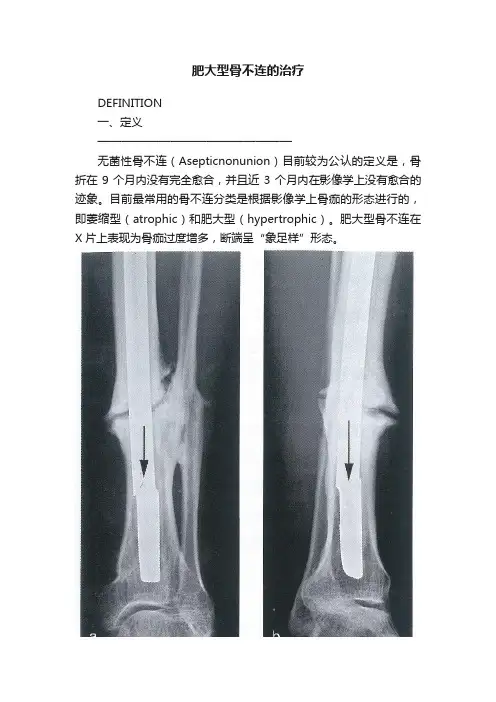

肥大型骨不连的治疗DEFINITION一、定义————————————————无菌性骨不连(Asepticnonunion)目前较为公认的定义是,骨折在9个月内没有完全愈合,并且近3个月内在影像学上没有愈合的迹象。

目前最常用的骨不连分类是根据影像学上骨痂的形态进行的,即萎缩型(atrophic)和肥大型(hypertrophic)。

肥大型骨不连在X片上表现为骨痂过度增多,断端呈“象足样”形态。

图1. 肥大型骨不连。

36岁男性,胫骨髓内钉固定19年后,肥大型骨不连,髓内钉疲劳折断。